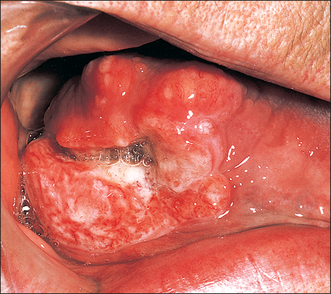

Erythroplakia (Fig. 10.2)

Erythroplakia is defined as ‘any lesion of the oral mucosa that presents as bright red velvety plaques which cannot be characterized clinically or pathologically as any other recognizable condition’. Such lesions are usually irregular in outline, although clearly demarcated from adjacent normal epithelium. The surface may be nodular. In some cases erythroplakia coexists with areas of leukoplakia. The incidence of malignant change in erythroplakias is 17 times higher than that in leukoplakia. In nearly every case of erythroplakia there are areas of epithelial dysplasia, carcinoma-in-situ or invasive carcinoma. Clearly all erythroplakic areas must be completely excised, either surgically or with a CO2 laser, and the specimens submitted for careful histological examination.

Fig. 10.2 Erythroplakia of the lateral border of the tongue.